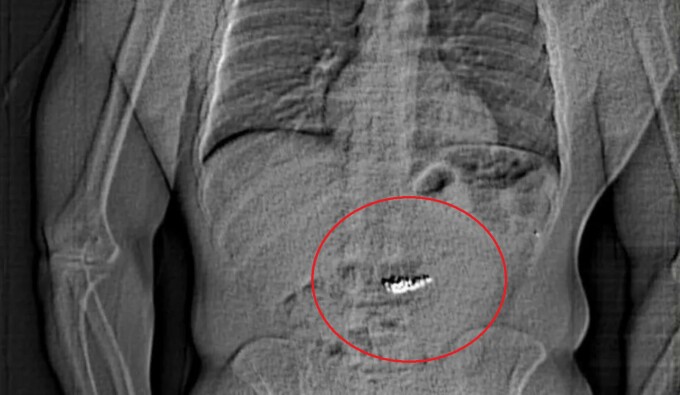

Poliția a publicat ulterior o radiografie care arată un obiect străin în abdomenul unui individ. Întrebați de BBC, reprezentanții Poliției din Orlando nu au precizat dacă bijuteriile au fost recuperate.